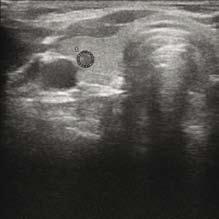

如果沒有可疑症狀,則需要做鼻咽喉內窺鏡檢查。要是發現頭頸部有惡性腫瘤(圖一是內窺鏡檢查,可見鼻咽癌),需要取組織做病理確診,然後再施以針對性治療。如果鼻咽喉內窺鏡檢查沒有發現腫瘤,需要做頸部超聲波檢查,包括腮腺、頜下腺、甲狀腺。如發現可疑病變,可進一步用超聲波導引抽取細胞病理確診(圖二是超聲波檢查,圓點所示為甲狀腺癌)。如果超聲波檢查沒有找出病原,需用超聲波導引抽取淋巴細胞做病理分析。如果淋巴細胞病理分析結果仍然未能確診,便需做手術拿取淋巴做病理切片分析,確診後便可進行針對性治療(圖三是頸淋巴癌的病理切片)。

圖二